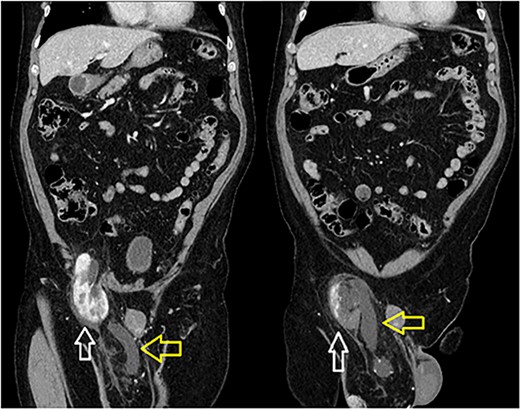

A 66-year-old Hispanic male presented to our emergency department with 1 week of right groin pain and swelling. He came to the hospital due to worsening pain. He denied any nausea, emesis or fever. He was passing gas and having bowel movements without difficulty. He denied any issues with voiding, hematuria or urinary urgency. His past medical history includes congenital deformity of his left upper extremity and past surgical history of open left inguinal hernia repair. His BMI is 32.5. His serum creatinine was 1.40 mg/dL. He had a normal white blood cell count at 9.8 × 103/UL and hemoglobin at 14.1G/DL. On examination, he had right inguinal tenderness to palpation with an obvious hernia extending to the scrotum. No skin changes were present. We were unable to reduce the hernia at bedside due to pain. A computed tomography (CT) of abdomen and pelvis with IV contrast showed herniation of the right kidney in the right inguinal hernia with the upper pole in the inguinal canal. The right renal artery and vein arose from the aorta and inferior vena cava, respectively, around the level of L1-L2 region (Fig. 1). The right ureter was incarcerated within the hernia and dilated up to 2 cm in diameter. The ureter transitions to normal caliber as it exits the hernia, concerning for obstructive uropathy (Fig. 2).

Sequential coronal CT with IV contrast. Left image showing renal artery (red) and vein (blue) arising from abdominal aorta and IVC. Right image showing descending vessels going into the incarcerated right kidney.

Incarcerated right kidney (white) in the inguinal hernia with distended ureter within the hernia sac (yellow).